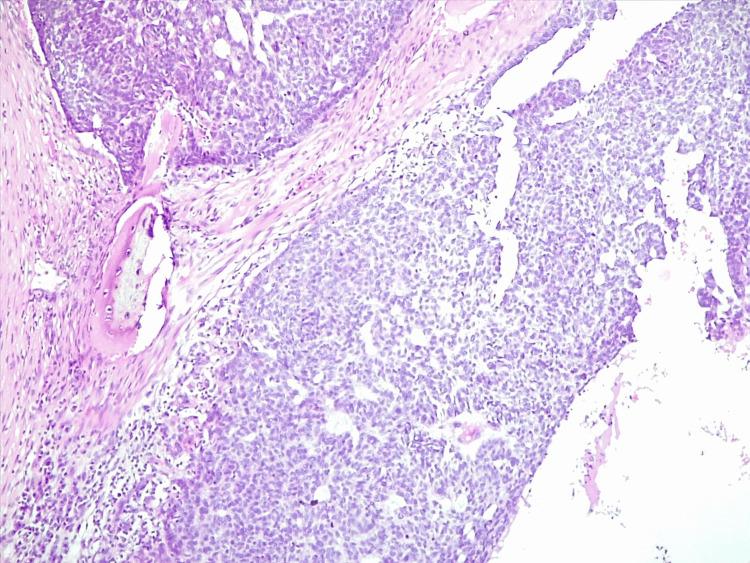

This case discusses an 85-year-old patient with a history of cataract causing severe right eye vision impairment and repeated surgeries for a basal cell carcinoma (BCC) on the right temple and its local recurrences (wide local excision in 2010; re-excision and reconstruction with a skin graft in 2017), who presented with progressive growth and extension of the skin tumour. Upon examination, an irregular, erythematous plaque with multiple ulcerations on the surface (the largest measuring 4 × 3 cm on the left temple) was observed. The lesion extended from one temple to the other, over the forehead, along the margins of the surgical skin graft, and invaded the upper left eyelid, with a protruding mass extending out of the orbit. A punch skin biopsy of the largest ulceration revealed basal cell carcinoma, infiltrative subtype, with areas of bone invasion. Given the difficult clinical scenario, the complex anatomical location, and the potential morbidity associated with surgery, the patient was deemed suitable for radiotherapy after a thorough evaluation. The patient showed good tolerance to treatment, with mild radiodermatitis managed topically, and achieved a satisfactory therapeutic response. Clinical and radiological evaluations demonstrated substantial regression in lesion size, no significant toxicities, and preservation of vision in the left eye. This case highlights the successful use of palliative radiotherapy in a patient with recurrent giant basal cell carcinoma of the upper face with orbital invasion, achieving eyesight preservation when surgery or systemic therapy were not viable options. Radiotherapy is emerging as a valuable treatment option for recurrent basal cell carcinoma in challenging anatomical locations. However, careful monitoring and rigorous treatment planning are essential forachieving favourable outcomes while minimizing side effects.

本病例讨论了一位85岁的患者,该患者有白内障病史,导致右眼严重视力受损,曾因右颞部基底细胞癌(BCC)及其局部复发接受多次手术(2010年进行广泛局部切除;2017年再次切除并进行皮肤移植重建),此次出现皮肤肿瘤进行性生长和扩展。检查时,观察到一个不规则的红斑性斑块,表面有多处溃疡(左颞部最大尺寸为4×3厘米)。病变从一侧颞部延伸至另一侧,越过前额,沿着手术皮肤移植边缘,侵犯左上眼睑,有一个突出的肿块延伸出眼眶。对最大溃疡处进行皮肤穿刺活检显示为浸润性基底细胞癌亚型,伴有骨侵犯区域。鉴于临床情况复杂、解剖位置特殊以及手术可能带来的并发症,经全面评估后,该患者被认为适合接受放疗。患者对治疗耐受性良好,局部处理了轻度放射性皮炎,获得了满意的治疗效果。临床和影像学评估显示病变大小显著缩小,无明显毒性反应,左眼视力得以保留。本病例突出了姑息性放疗在一名复发性巨大面部基底细胞癌伴眼眶侵犯患者中的成功应用,在手术或全身治疗不可行的情况下实现了视力保留。放疗正逐渐成为在具有挑战性的解剖位置复发性基底细胞癌的一种有价值的治疗选择。然而,仔细监测和严格的治疗计划对于在最小化副作用的同时取得良好疗效至关重要。